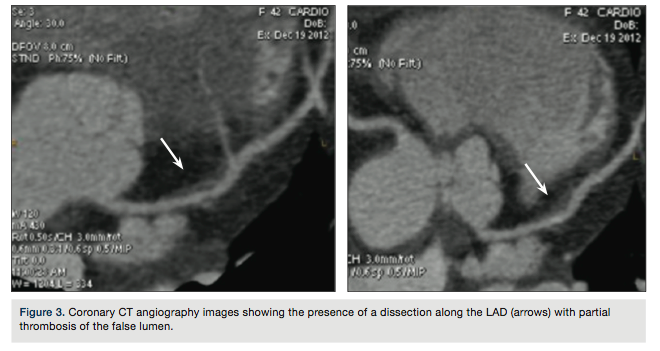

To provide a better anatomic definition of the dissection, coronary CT angiography was

performed 7 days after admission (Figure 3) showing the presence of a dissection along the LAD (arrows) with partial thrombosis of the false lumen. At this point, the patient was discharged.